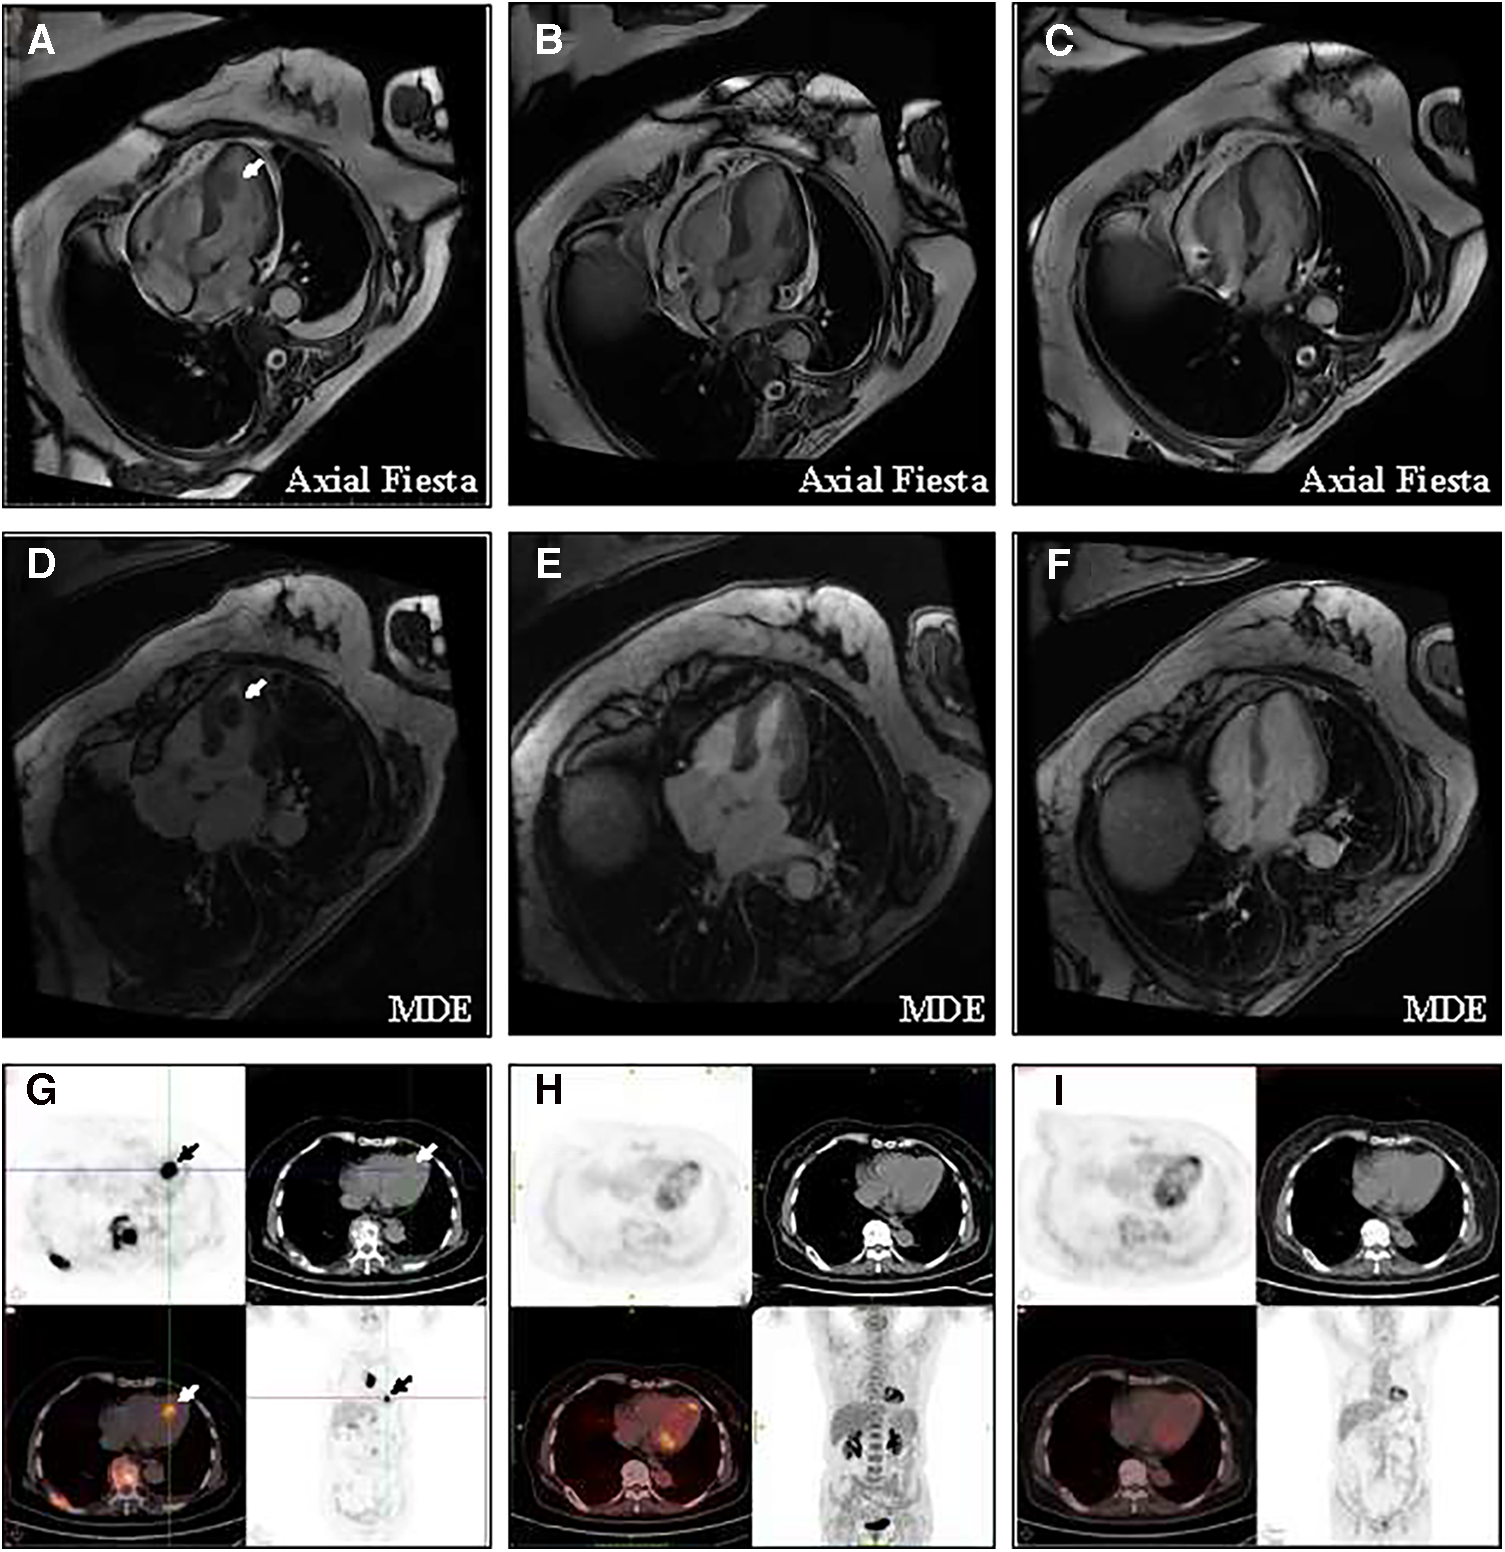

Rituximab plus cyclophosphamide, doxorubicin, vincristine, and prednisone (R-CHOP) was treated immediately as first-line therapy. Almost all sites of tumor lesions were significantly reduced after two cycles of R-CHOP. The left ventricular mass was reduced to 1.1 cm × 0.6 cm, and the pain and temperature sensation below the level of the 4th thoracic vertebra were normalized, and the muscle strength of the left and right lower limbs improved to levels 4 and 5, respectively. After 4 cycles of R-CHOP, the left ventricular mass had almost regressed and the muscle strength of both lower limbs had completely returned to normal. A total of 6 cycles of R-CHOP were completed for first-line treatment, and the efficacy evaluation was complete response and then follow-up. During the treatment period, the LVEF increased from 65% at baseline to 69%, and no cardiovascular-related adverse events were observed. During the 5-year follow-up, all lesions, including the cardiac mass, remained complete regression, and FDG uptake was reduced to normal (Figure 2). The patient was able to walk normally and had no tumor-related symptoms. At the time of this manuscript (more than 5 years from follow-up), she is alive and has normal functional capacity. Despite the patient receiving anthracycline-based chemotherapy in first-line treatment, the LVEF remained normal, and no long-term cardiovascular toxicity was observed at 5 years of follow-up.

Figure 2

Change of the left ventricular mass at baseline and after treatment (A) CMR showed that the baseline size of the mass is 1.6 cm × 1.1 cm × 2.1 cm. (B) CMR showed that after 4 cycles of R-CHOP, the tumor at all sites had almost complete regression. (C) CMR showed no recurrence of cardiac mass in the five years of follow-up. (D) Long-axis four-chamber myocardial delayed enhancement (MDE) showed that the left ventricular mass appeared non-gadolinium enhancement at baseline. (E) After 4 cycles of R-CHOP treatment, long-axis four-chamber MDE showed the left ventricular mass had almost complete regression. (F) MDE showed no recurrence of cardiac mass in the five years of follow-up. (G) PET/CT showed that the maximum standardized uptake value for left ventricular masses was 16.5 and 19.7 after delay. (H) After 4 cycles of R-CHOP treatment, the left ventricle mass had almost complete regression and the FDG uptake of the left ventricular had returned to normal levels. (I) PET/CT showed no recurrence of cardiac mass in the five years of follow-up.